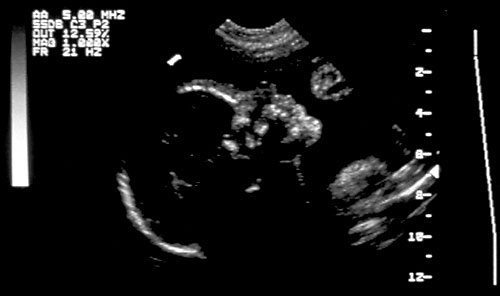

Normal cervical spine at 18 weeks (1). Another normal sagittal view of cervical spine seen in third trimester with folds of fat seen (2). Normal thoracic spine at 18 weeks (3). Normal sagittal view of lumbosacral spine at 18 weeks (4). Normal transverse view of lumbosacral spine at 18 weeks (5). - Extremities (hands/feet)